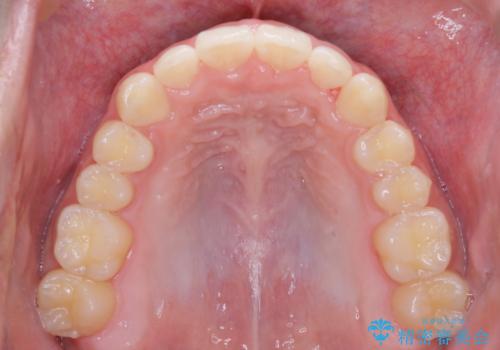

- 上の前歯が見えすぎて気になるとご相談にいらした方です。インビザラインにて前歯の圧下を行うことで歯の見え方の改善し、同時に奥歯の噛み合わせも改善を行いました。

インビザラインを正しく使用して頂けたおかげで、比較的難しいとされる歯の圧下も補助装置を使用せずに行うことが出来ました。上の前歯のラインが整ったことで笑った時の口元の印象を改善させることができ、大変喜んでいただけました。